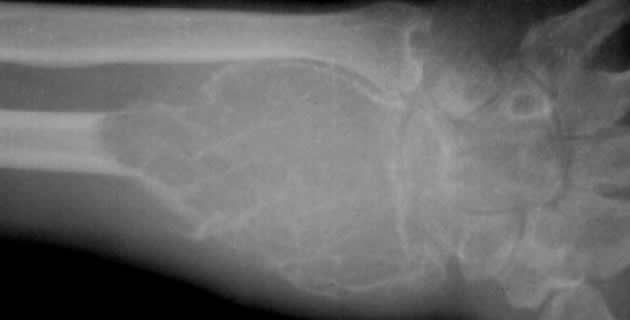

Od simptoma bolesnici se najčešće žale na bol, a kod nekih nema simptoma do nastanka patoloških fraktura. RTG snimkom vidljive su karakteristične promjene oštrih granice bez sklerotičnih žarišta “mjehurići poput sapunice”, osteoliza bez periostalne reakcije. Ako je zahvaćen zglob, dolazi do proboja kosti i može zahvatiti i ligamente. Često recidivira lokalno, a maligna alteracija (u 10% slučajeva).